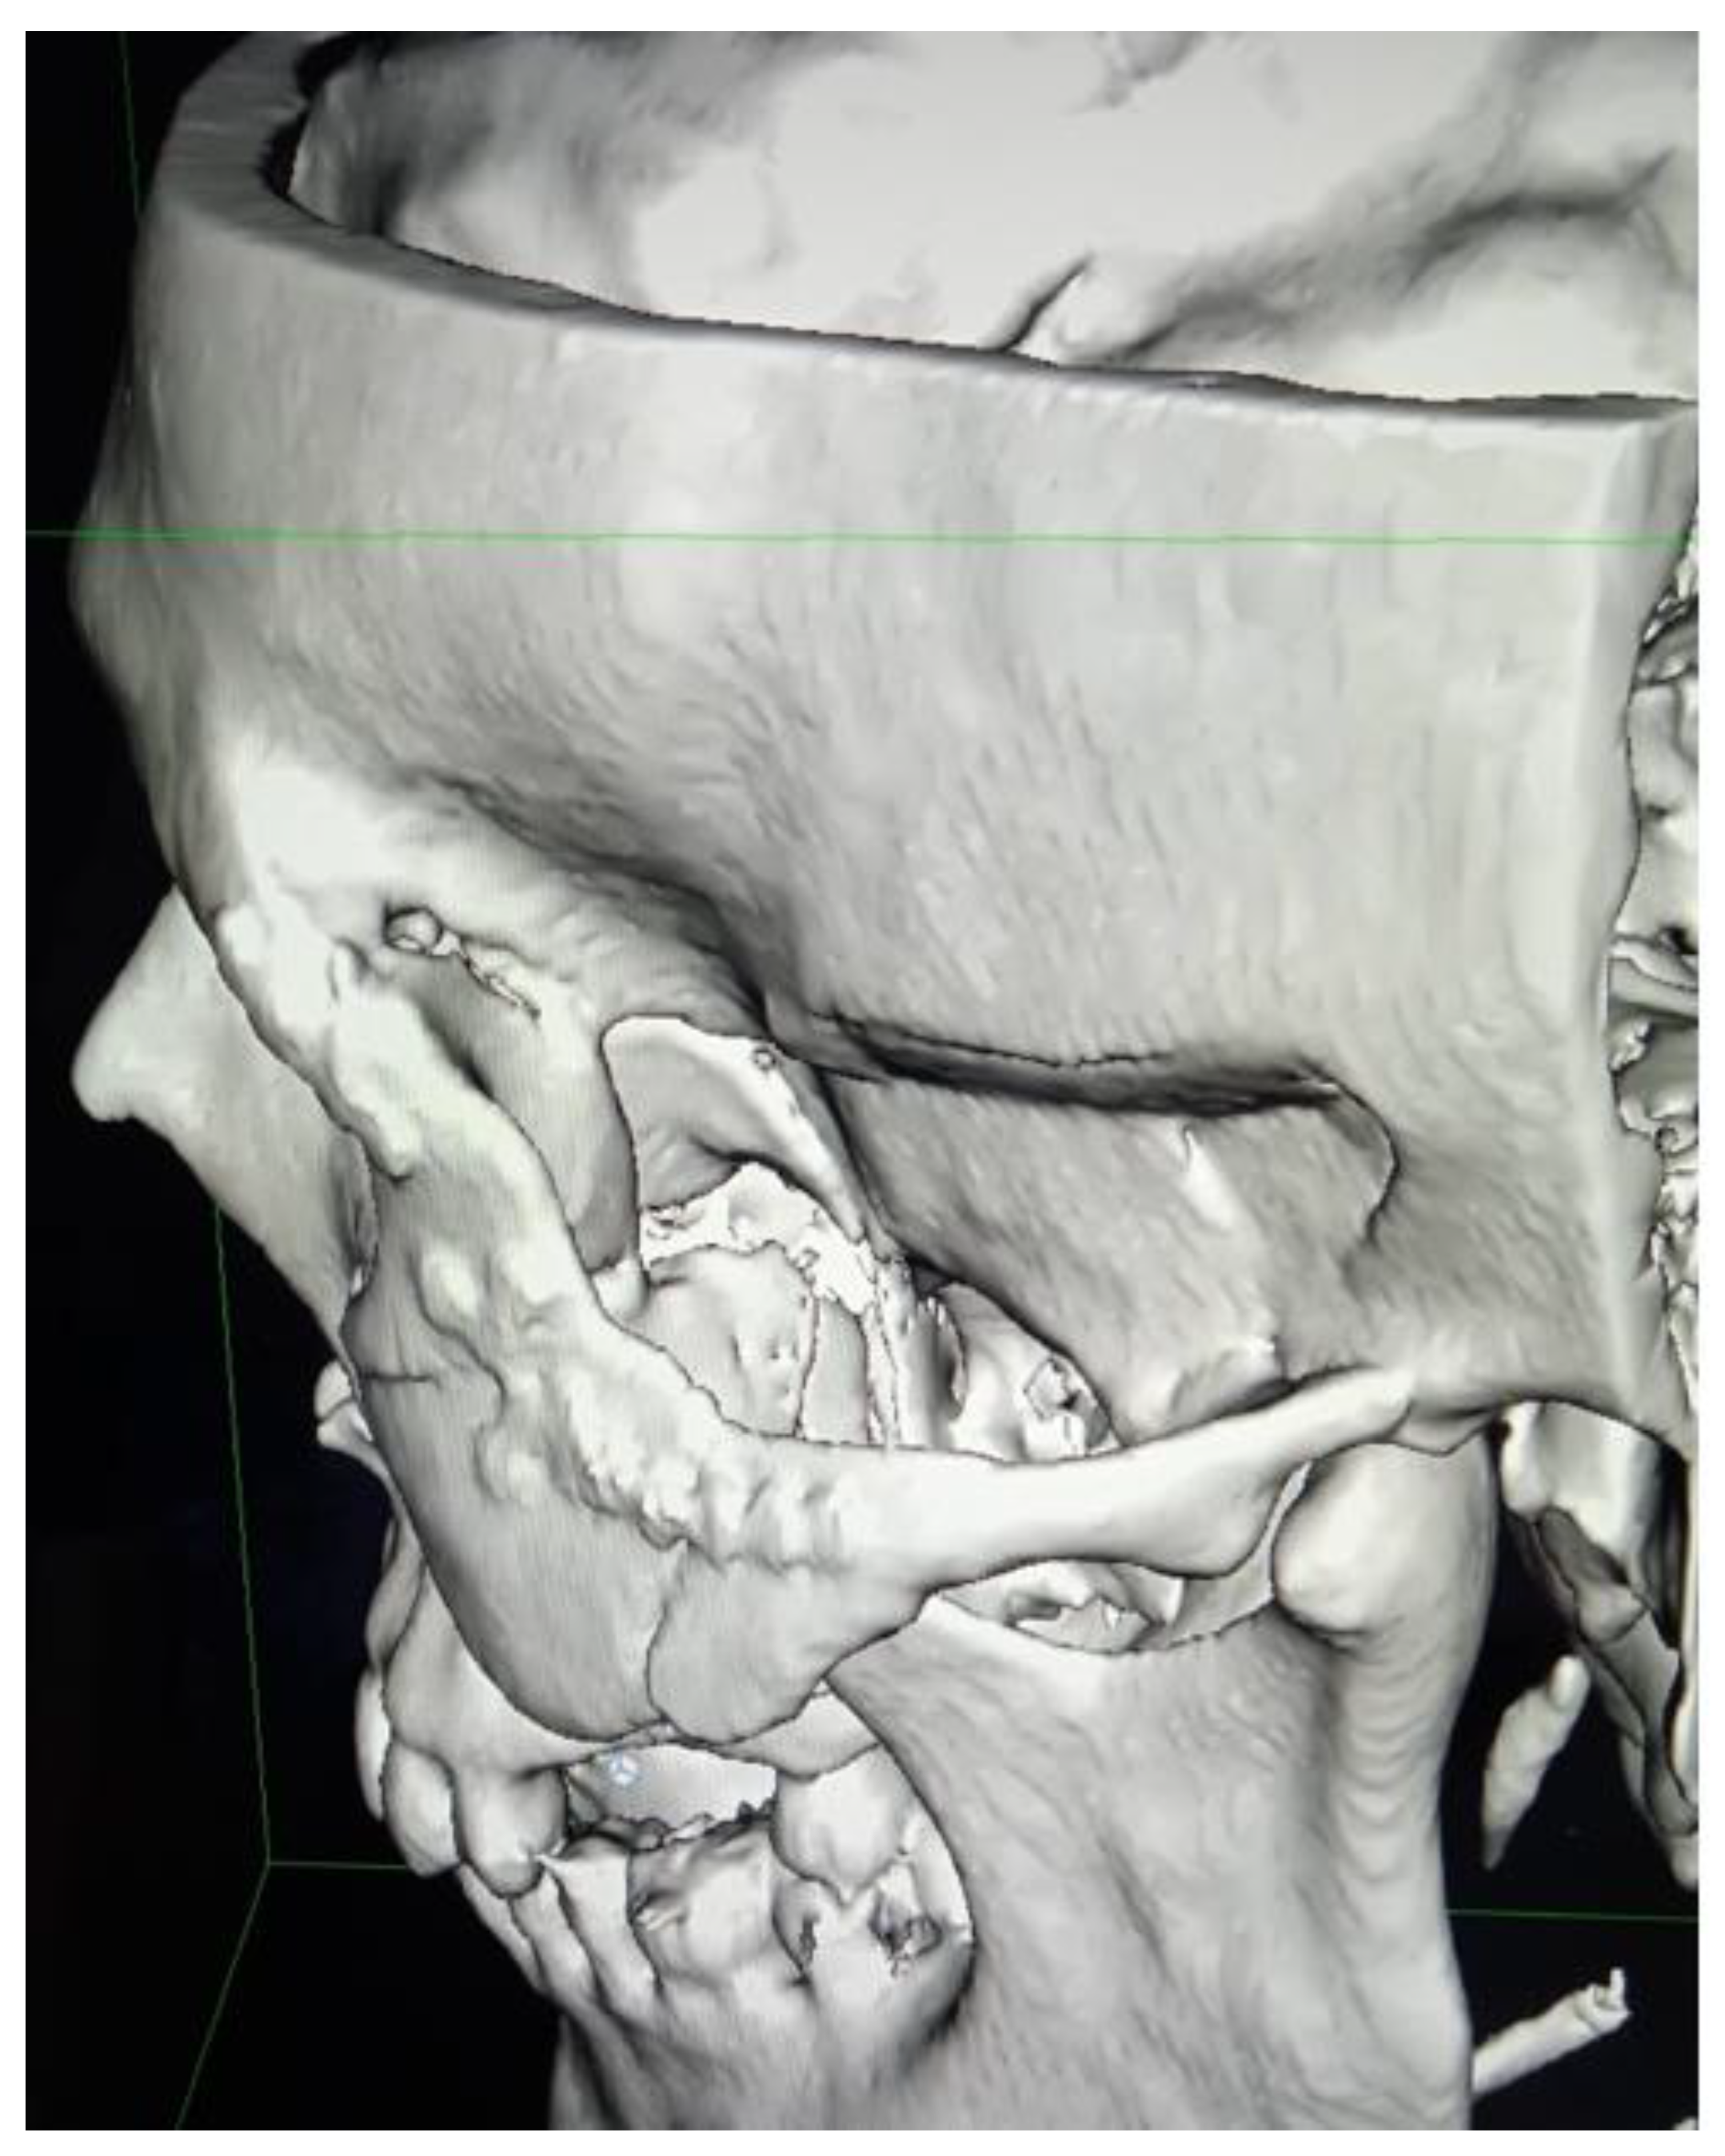

Figure 15. Postoperative fronto-lateral view on 3D-CT evaluation.